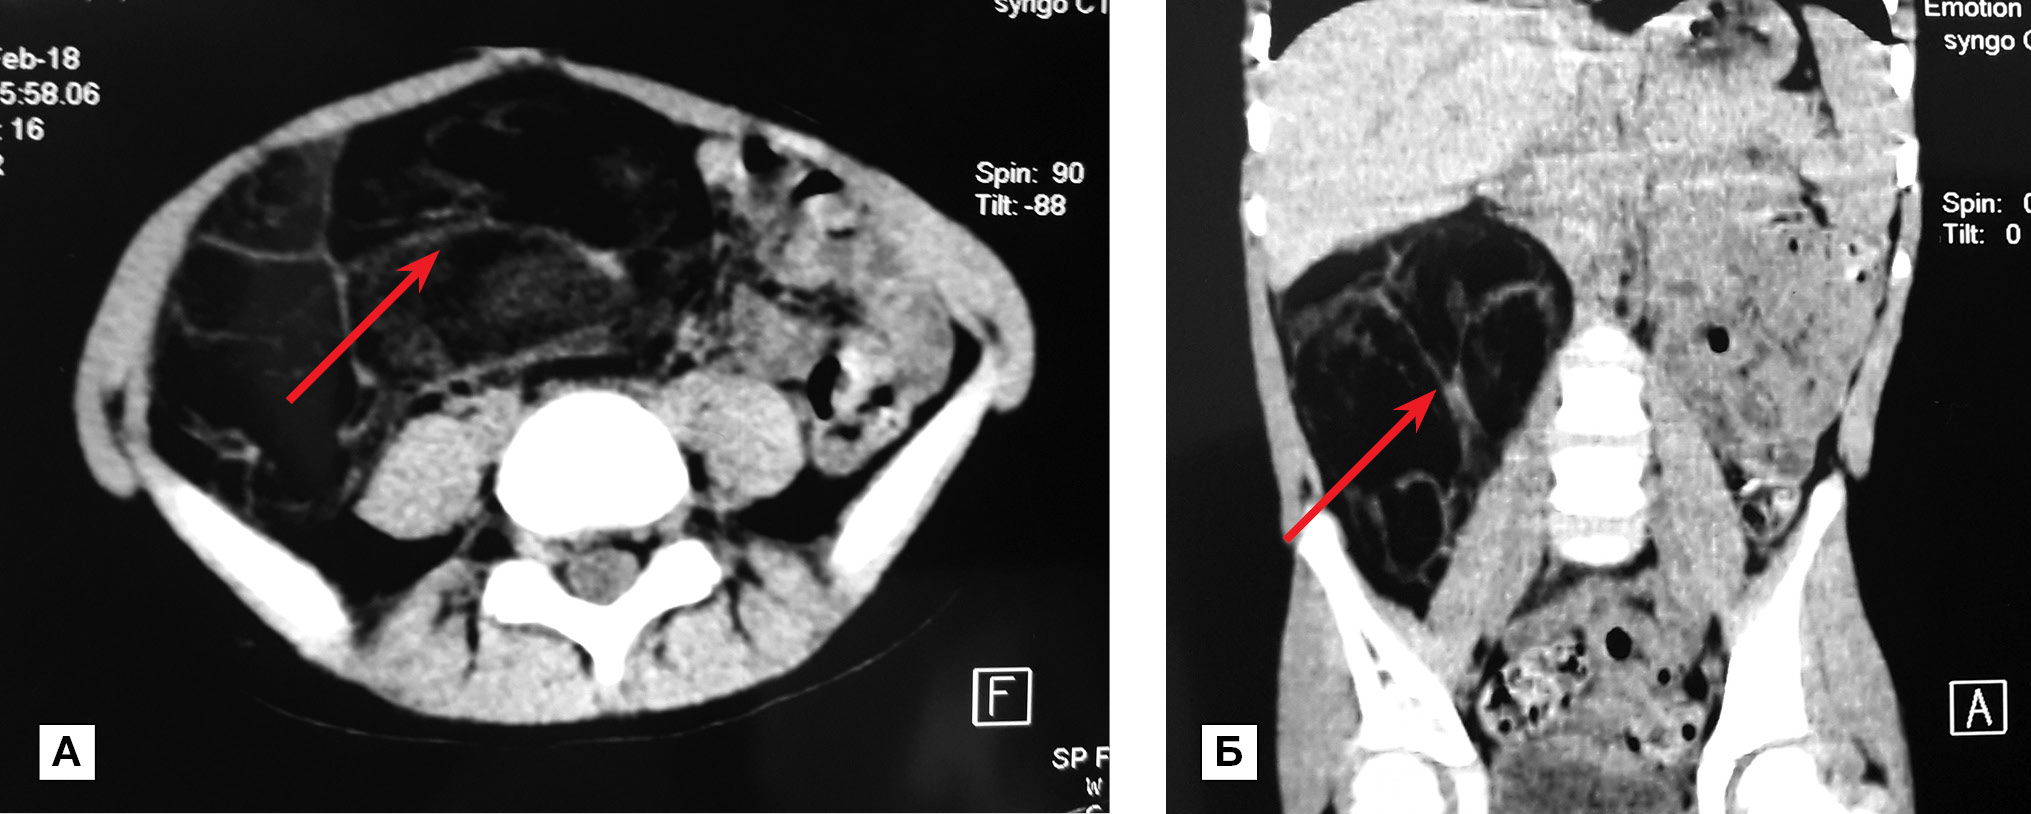

- компьютерная томография органов брюшной полости (рис. 1): в проекции забрюшинного пространства справа определяется образование с четкими контурами, неоднородной структуры за счет наличия множественных перегородок, в основной массе жировой плотности от -12 до -75 едН, максимальными размерами 15,2×13,6×7,3 см, пролабирующее в правую половину брюшной полости. Картина забрюшинного образования справа. Гигантская липома (?)».

Рис. 1. Компьютерная томография органов брюшной полости в трансверзальной (А) и фронтальной (Б) проекциях. Забрюшинное образование справа (показано стрелкой)